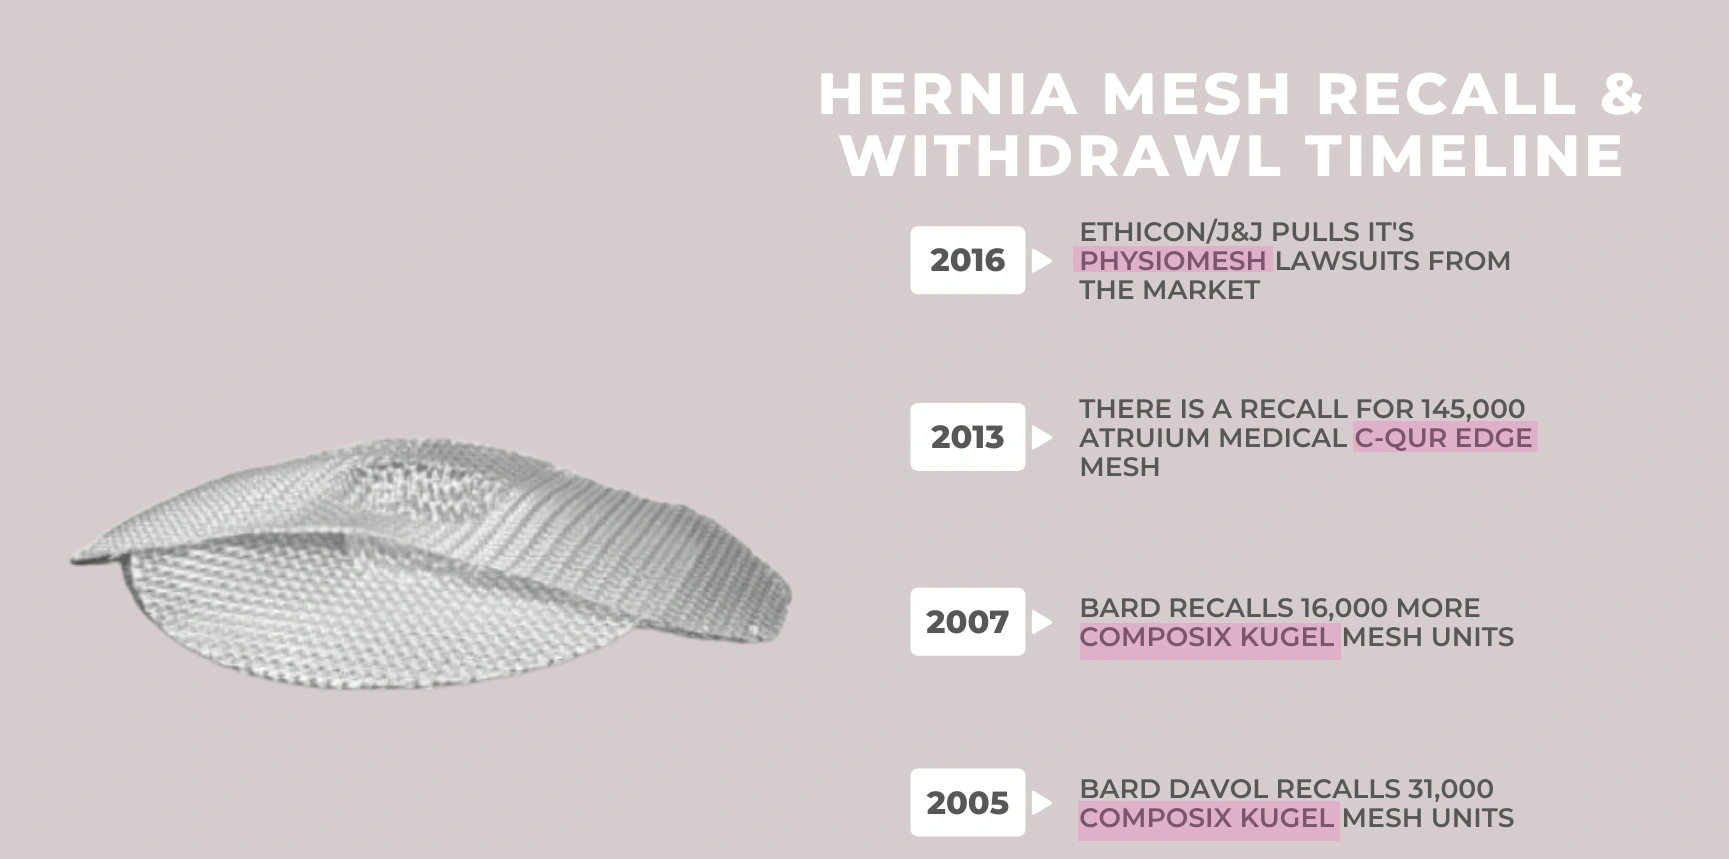

Wadliwe siatki przepuklinowe

Bywa, że w pogoni za zyskami firmy wprowadzają do sprzedaży niedostatecznie sprawdzone produkty medyczne. Dotyczy to też siatek przepuklinowych. Firmy mają o co walczyć: rocznie na świecie sprzedaje się siatki przepuklinowe za 4,7 miliarda dolarów.

Po pewnym czasie okazuje się pacjenci, u których zastosowano nową siatkę mają często powikłania (np.: bóle, ropienie ran, itd). Lekarze widzą gorsze wyniki operacji. W Polsce przechodzi to prawie niezauważone; często pretensje są raczej do lekarzy.

W USA takie sytuacje kończą się procesami sądowymi przeciw producentom wadliwych siatek.

Procesy w USA przeciw producentom siatek do przepuklin styczeń 2024 (niektóre)